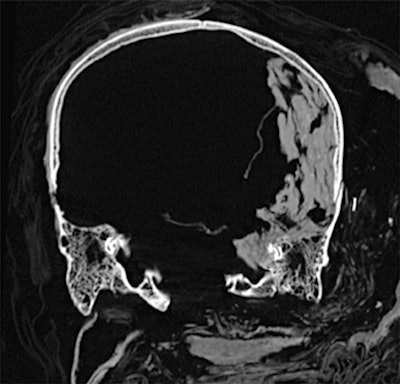

Dr. Sahar Saleem, a professor of radiology at Cairo University who specializes in CT mummy imaging, and archeologist Zahi Hawass, PhD, have used CT scans and 3D reconstructions to suggest he had multiple killers. They have presented their findings in an article published on 17 February in Frontiers of Medicine that received over 10,500 page views by February 21.

CT revealed details of the head injuries, including wounds that had not been discovered in previous examinations and had been skillfully hidden by the embalmers. The mummy's deformed hands indicate that Seqenenre may have been captured on the battlefield, and his hands were tied behind his back, preventing him from deflecting the fierce attack on his head.

The CT scans, combined with other evidence, suggest the execution was carried out by multiple attackers, which the scientists confirmed by studying five different Hyksos weapons that matched the king's wounds. The study also determined that Seqenenre was about 40 when he died, based on the detailed morphology revealed in the images, providing the most precise estimate to date, according to the authors.

In addition, the investigation revealed details about the mummification of Seqenenre's body. For instance, the embalmers used a sophisticated method to hide the king's head wounds under a layer of embalming material that functioned similarly to the fillers used in modern plastic surgery. This would imply that mummification took place in a real mummification laboratory rather than in a poorly equipped place, as previously interpreted.